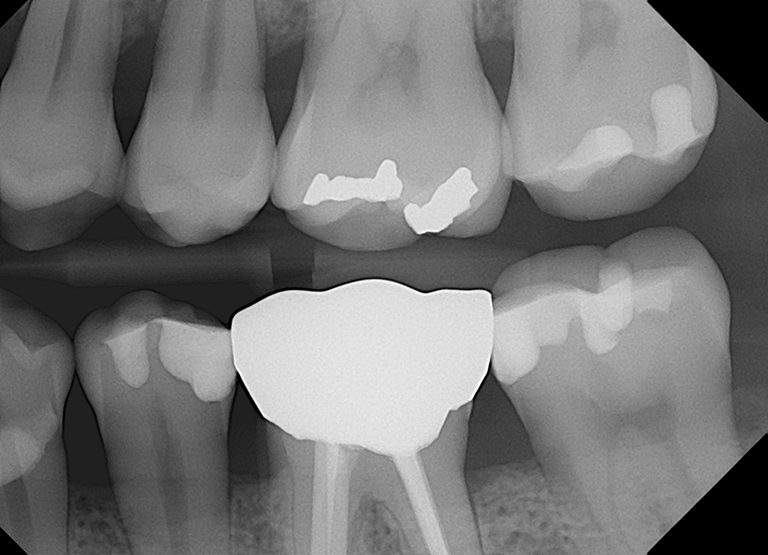

Our Open Sensor offers a cost-effective way to get high-quality x-ray images comparable to (or even better than) more expensive alternatives. It’s one of the thinnest dental x-ray sensors on the market, and integrates seamlessly with leading imaging software.

Product Specifications:

| Size 0 | Size 1 | Size 1.5 | Size 2 | |

|---|---|---|---|---|

| Active Area | 18mm x 24mm | 20mm x 30mm | 24mm x 33mm | 26mm x 36mm |

| Sensor Thickness | 4.5mm | |||

| Resolution | 20 line pair/mm actual, 25 line pair/mm theoretical | |||